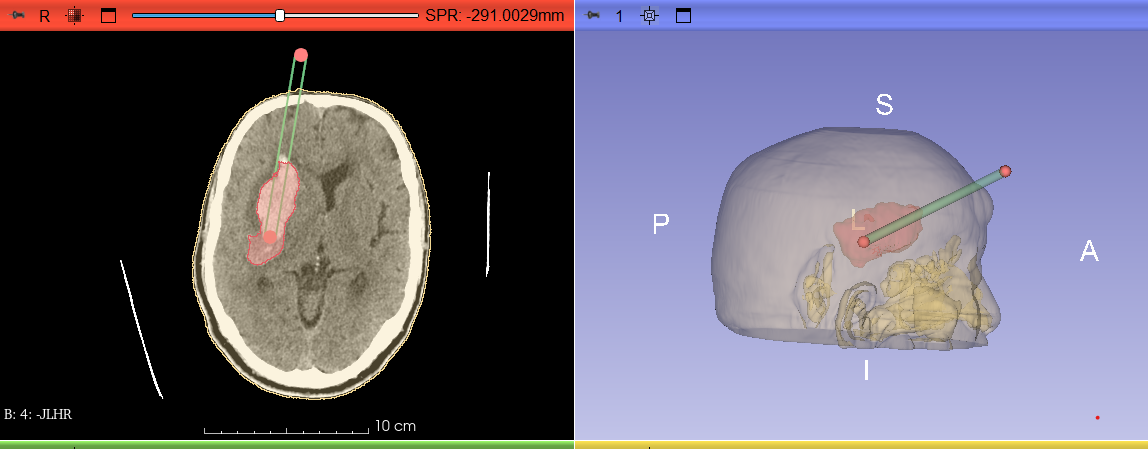

1.三维重建,虚拟规划:术前,医生将患者的颅脑CT数据输入计算机,生成一个颅内三维数字模型,血肿的形态、深度及其与关键组织的比邻关系清晰呈现。

3.精准引导,一击即中:手术中,这枚特殊的“GPS”导板稳固贴合在患者头部,为手术穿刺针提供精确的进针角度和深度通道,穿刺导管沿此通道进入,直达血肿中心,实现毫米级的精准定位。